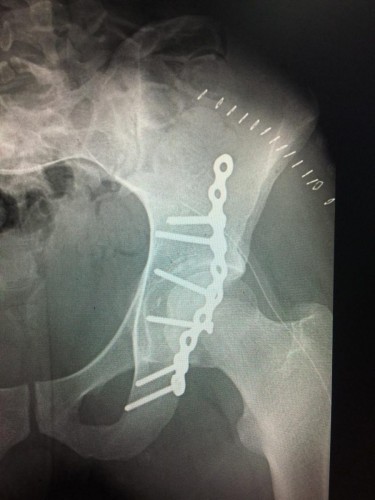

واصل مستشفى القريات العام ، نجاحه بإجراء عدد من العمليات بعد أن سجل مؤخراً نجاح عملية جديدة في جراحة العظام ،

فقد تمكن بفضل الله فريق طبي بقسم جراحة العظام في المستشفى من إجراء عملية تثبيت جراحي‫ بشريحة اعادة بناء مع براغي‬

لـمريض يبلغ من العمر 21 عاماً أُصيب بها جراء حادث مروري ،

دخل على أثرها المستشفى لتلقي العلاج وعلى الفور قام الفريق الطبي بإجراء عملية عاجلة لعلاج الكسور ، حيث كانت الإصابة ‫كسر بالجوف المفصلي للحوض‬ الأيسر

وقد تم ولله الحمد التثبيت الجراحي بشريحة إعادة بناء مع براغي ، علماً أنها من العمليات الكبيرة التي يتم إجرائها بالمستشفيات التخصصية الكبرى حيث تم إجرائها بمستشفى القريات العام